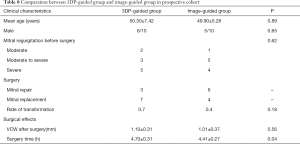

Prospective cohort

Mean age, sex, and severity of MR in the 3DP-guided group and image-guided group were not statistically different. Mitral repair was done for 3 patients in the image-guided group and 6 patients in the 3DP-guided group. Although not statistically different, the rate of transfer to replacement was significantly lower in the 3DP-guided group (Table 8). Surgery time was also lower in the 3DP-guided group. No complications occurred in either group.